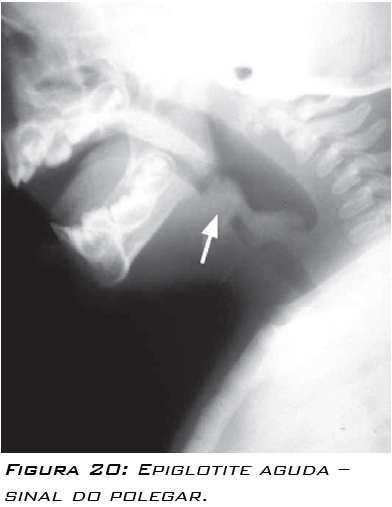

O sinal radiológico descrito para epiglotite aguda é denominado “sinal do polegar”, observado na radiografia cervical lateral, explicado pelo edema da epiglote. Este exame não deve ser solicitado quando o quadro clínico indica que se está diante de uma epiglotite aguda, pois qualquer demora na obtenção da via aérea piora o prognóstico do paciente.

É descrito que a radiografia cervical lateral pode ser solicitada quando há suspeita do diagnóstico, mas este parece duvidoso. Porém, se o exame for solicitado, a criança deverá estar o tempo toda acompanhada por alguém capaz de realizar a intubação traqueal, caso seja necessário.